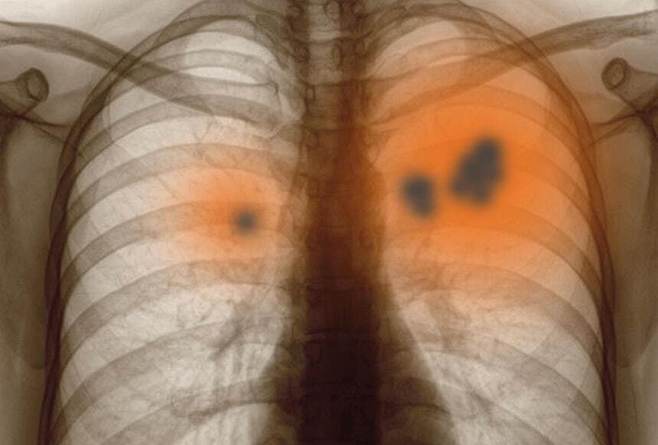

국내 암 사망자 10명 중 2명은 '폐암'이 원인이다. 전체 암 중 폐암의 사망률이 가장 높다. 폐암의 주 원인은 흡연으로 알려졌지만, 비흡연자라고 해서 안심은 금물이다. 실제 국내 폐암 환자의 약 40%가 비흡연자다. 국내 여성 폐암 환자의 88% 가량이 비흡연자라는 통계도 있다. 이에 정부는 국민 폐 건강 관리에 나섰다. 내년부터 56살, 66살 국민은 국가건강검진에서 폐기능 검사를 받을 수 있게 됐다.